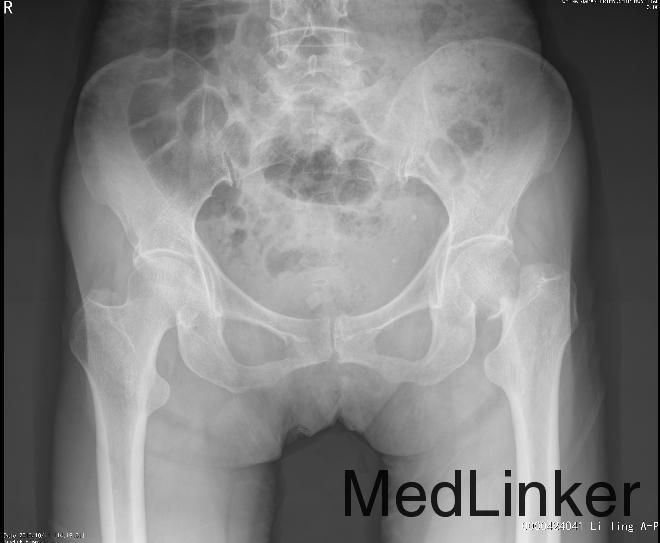

患者,女,62岁,主因“摔伤后左髋部疼痛伴活动受限1天”入院。患者昨日于家中活动时不慎摔伤,左髋部着地,遂感左髋部剧痛,不能自行站起,被家人送至我院急诊科就诊,行X线检查后诊断为"左股骨颈骨折",予左下肢皮牵引等处理。现患者为行进一步治疗,以“股骨颈骨折”收入我科。

查体:平车推入病房。左下肢屈曲、外旋畸形,较右下肢短缩约2cm。左髋部无明显肿胀,腹股沟中点及左髋外侧压痛(+),左下肢轴向叩击痛(+)。左髋关节活动受限。 辅助检查:左髋关节正侧位X线:左侧股骨颈骨折,完全移位。

诊断:左侧股骨颈骨折(Garden Ⅳ型) 治疗:行左侧全髋关节置换术